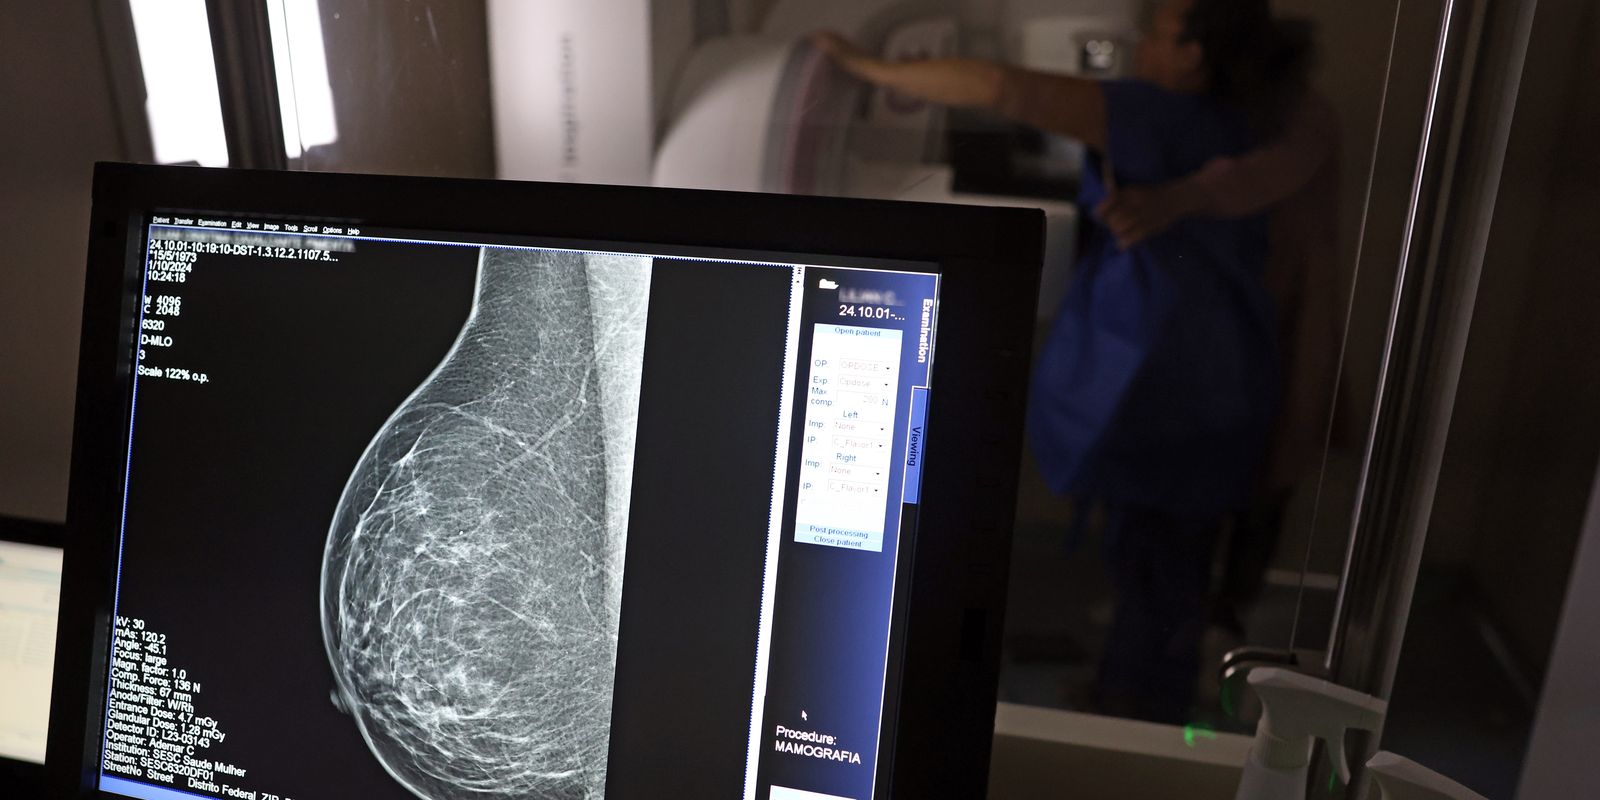

Uma nova lei, publicada nesta segunda-feira (6), reforça o direito do trabalhador com contrato via Consolidação das Leis do Trabalho (CLT) de se afastar até três dias por ano para realizar exames preventivos de câncer, em desconto salarial.

Uma nova lei, publicada nesta segunda-feira (6), reforça o direito do trabalhador com contrato via Consolidação das Leis do Trabalho (CLT) de se afastar até três dias por ano para realizar exames preventivos de câncer, em desconto salarial.

O direito já estava incluído na CLT desde 2018. A partir de agora, as empresas passam a ser obrigadas a divulgar essa informação, além de outras relacionadas a campanhas oficiais de vacinação contra o HPV e sobre o acesso a serviços de diagnósticos de cânceres de mama, próstata e de colo do útero.